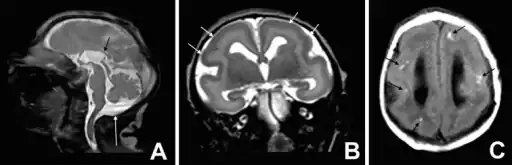

a-c)T1 and T2 image- microlissencephaly

MRI of a patient with a TUBA1A mutation showing microlissencephaly with cerebellar hypoplasia. a. smooth brain surface (arrow) b. absent corpus callosum (arrow).